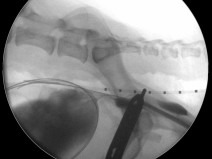

• Radiologie interventionnelle : se lancer et voir plus loin !

Le Groupe d'Étude en Chirurgie est heureux d’organiser sa 9è journée spécialisée sur le thème de la radiologie interventionnelle, le 29 janvier 2026. Cette journée annuelle de formation vise un public de vétérinaires ayant un fort intérêt pour la chirurgie des tissus et la chirurgie mini-invasive. Elle se tiendra au siège de l'AFVAC Paris 8è.

Cette année, nous avon...

Le 29 janvier 2026

Paris (75008)

Chirurgie

Oncologie

G.E.C.

2080